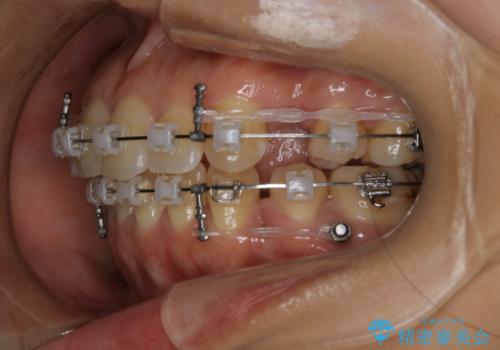

前歯を後ろに下げたい ワイヤー矯正(クリア装置)

- 矯正装置

- クリア装置

- 前歯を後ろへ下げることを主訴に来院された患者様です。

10代の時に非抜歯でワイヤー矯正をしていました。

口元の突出感の改善や歯の移動量などを考慮し、抜歯を伴うワイヤー矯正での治療を選択しました。

抜歯を行うことで前歯を後ろへ下げるスペースを獲得し、口元の突出感や歯のガタつきを改善していきました。